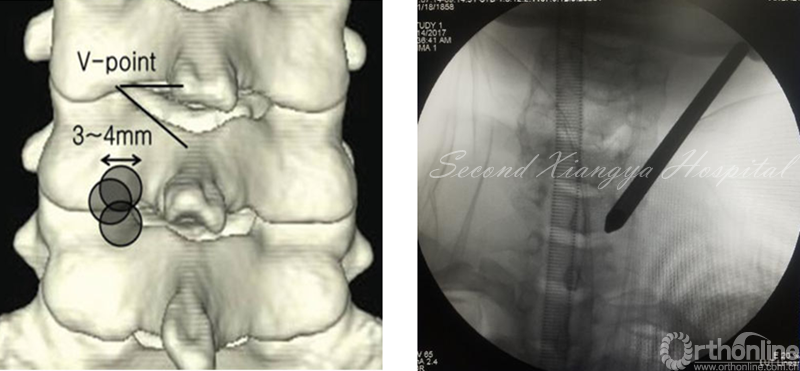

颈椎后路锁孔:颈椎后路结构单一,穿刺的靶点指向病变节段上椎板下缘、关节突和下椎板上缘组成的“V”点偏外骨性结构,穿刺端避免偏内落入椎管误伤脊髓。

同时,侧位透视时应调整C-Arm角度,也可通过C臂聚焦来显露被肩胛骨遮挡的下颈椎区域,从而帮助准确定位手术节段和防止穿刺后工作套管置入过深。

颈椎后路椎间孔入路:

颈椎后路经椎间孔入路骨性标志点为“V”点,操作时注意“靶区触骨,动力先行,显根上下,脊髓勿碰。”也就是说,建立靶区应落到V点骨性结构部分,再用动力沿V点磨除外层皮质骨,黄韧带边缘会自然显露,再用Kerrison钳扩大显露神经根肩部与腋部,用神经勾进行探查和髓核摘除,手术全程都要注意保护脊髓,避免通过后方进行椎间隙髓核摘除这一危险操作。